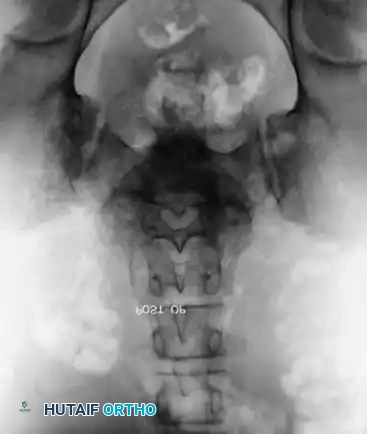

- Anteroposterior (AP) View: Evaluates for concurrent scoliosis and transverse process anatomy.

- Ferguson Coronal View: The X-ray beam is angled 30 degrees cephalad (parallel to the L5-S1 disc space). This provides a true en face view of the L5 pedicles, transverse processes, and sacral ala.

Comprehensive preoperative planning requires full-length standing scoliosis films to calculate pelvic parameters (Pelvic Incidence, Pelvic Tilt, Sacral Slope).